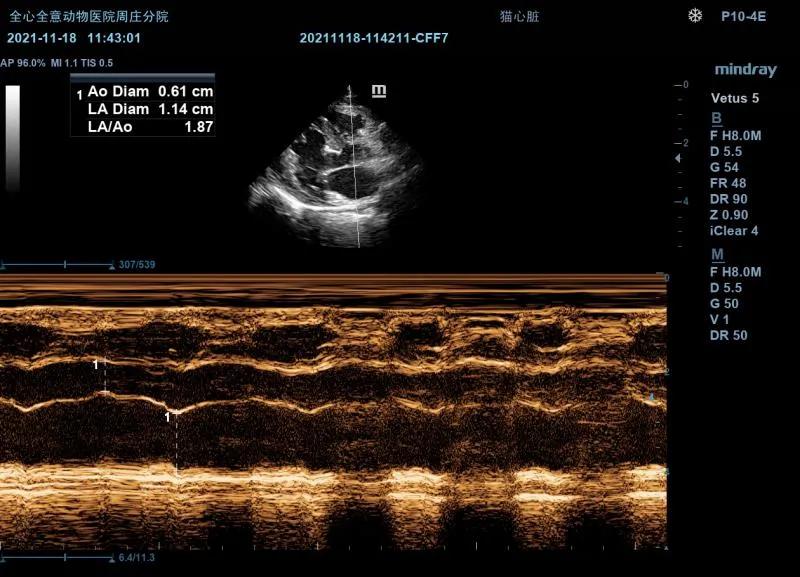

LA/AO:

右侧左室流出道观比:1.87(<2.5为正常)

右侧短轴二尖瓣观(M型):

EPSS:0.11cm

E-F Slope:4.23cm/s

C点至D点二尖瓣运动轨迹异常。